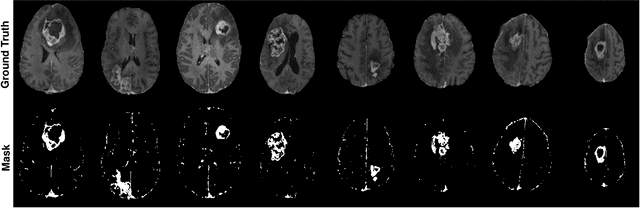

Abstract:Gadolinium-based contrast agents (GBCAs) have been widely used to better visualize disease in brain magnetic resonance imaging (MRI). However, gadolinium deposition within the brain and body has raised safety concerns about the use of GBCAs. Therefore, the development of novel approaches that can decrease or even eliminate GBCA exposure while providing similar contrast information would be of significant use clinically. For brain tumor patients, standard-of-care includes repeated MRI with gadolinium-based contrast for disease monitoring, increasing the risk of gadolinium deposition. In this work, we present a deep learning based approach for contrast-enhanced T1 synthesis on brain tumor patients. A 3D high-resolution fully convolutional network (FCN), which maintains high resolution information through processing and aggregates multi-scale information in parallel, is designed to map pre-contrast MRI sequences to contrast-enhanced MRI sequences. Specifically, three pre-contrast MRI sequences, T1, T2 and apparent diffusion coefficient map (ADC), are utilized as inputs and the post-contrast T1 sequences are utilized as target output. To alleviate the data imbalance problem between normal tissues and the tumor regions, we introduce a local loss to improve the contribution of the tumor regions, which leads to better enhancement results on tumors. Extensive quantitative and visual assessments are performed, with our proposed model achieving a PSNR of 28.24dB in the brain and 21.2dB in tumor regions. Our results suggests the potential of substituting GBCAs with synthetic contrast images generated via deep learning.